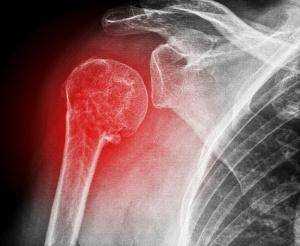

Боль в плече часто возникает на фоне неврологических и сосудистых заболеваний, однако причиной может быть и артроз плеча, а также системные заболевания плечевого сустава воспалительного характера. Рентген в основном назначают при подозрении на вывих или перелом. На снимке видны и соседние образования - ключицы и лопатки. Он информативен также при артрозе и артрите, некрозе плечевых головок, тендините и других заболеваниях.

Вывих головки плечевой кости

При такой патологической ситуации, как вывих головки плечевой кости, её поверхности полностью утрачивают контакт с поверхностями лопаточной кости. При этом под действием сместившихся костей может отмечаться разрыв суставной сумки и связочного аппарата в соответствующей области.

Рентген в двух проекциях (прямой и осевой) довольно чётко может показать отклонение текущего состояния плечевого сустава от нормы. На снимках можно увидеть, насколько смещена головка плечевой кости, каково направление её смещения, а также наличие переломов костей (если они есть). С помощью рентгена можно определить тип вывиха и предположить развитие возможных осложнений. Не допускается вправлять вывих без предварительного проведения рентгена.

Перелом шейки плечевой кости, боковой части лопатки или ключицы

Все кости на рентгене отображаются в виде плотных белых образований. Переломы костей, а также трещины на них выглядят на снимках как тёмные полосы, расположенные в различных направлениях и имеющие различную локализацию и размер. Фото-рентген плечевого сустава позволяет обнаружить наличие переломов плечевой кости, ключицы и лопатки. Снимок нужен для того, чтобы определить сложность перелома, увидеть, как расположены осколки костей (если имеет место раздробление).